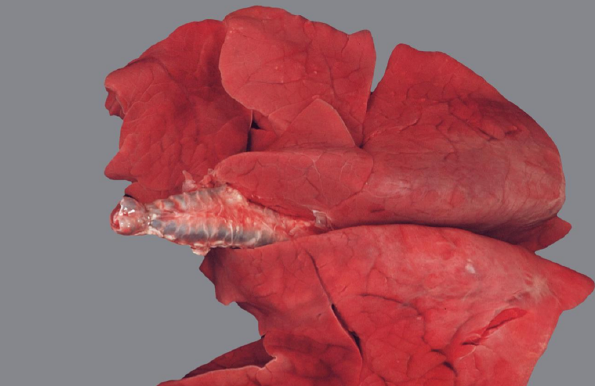

Beschreibung:

• Viszeral: Gallengänge stellen sich als weiße und derbe

Stränge dar

• hochgradig verdickte Wände von Gallengängen / die Wände

dieser Gallengänge sind hochgradig verdickt und

teilweise mineralisiert

• Adulte blatt-/lanzettförmige Trematoden (Pfeil) und

Gallekonkremente im Lumen

Diagnose:

• (Grad), Multifokale, chronischfibrosierende

Cholangitis und Pericholangitis mit

Gallengangsobstruktion

Fasziolose

Ätiologie:

• Rind und Schaf: Fasciola hepatica („großer Leberegel“)

Pathogenese:

• Chronische pericholangiäre und cholangiäre Fibrose durch in den größeren Gallengängen lebende Adulte

• Gallengangsobstruktion führt zur Stenose und Ektasie sowie periduktulärer Fibrose, im weiteren Verlauf zu Cholestase (Porphyrin-Eisen-

Pigmente)

Zusatzinfo:

• Entwicklung über Zwischenwirt (Lymnaea) → Tiere nehmen Metazerkarien aus Umwelt auf, Wanderung über Darm in Leber, dort ‘‘akute

Fasziolose‘‘ (Wanderwege zu den Gallengängen)

• Ausscheidung der Eier über die Galle